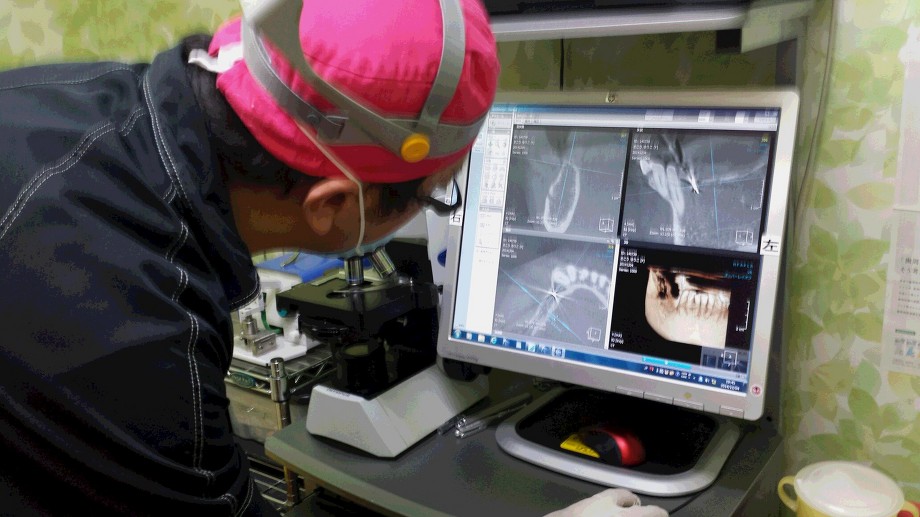

フジモン技工所は大阪市内で頑張っておられる研究熱心な歯科技工所であり、その代表のフジモンはお上品×10な奈良県よりもリアルで厳しい現場であるのでしょうか?自費専門だけのことがあり、かなり現実...今風にいうところの......リアルに鍛え抜かれているように感じられました。(笑)

フジモン技工所は大阪市内で頑張っておられる研究熱心な歯科技工所であり、その代表のフジモンはお上品×10な奈良県よりもリアルで厳しい現場であるのでしょうか?自費専門だけのことがあり、かなり現実...今風にいうところの......リアルに鍛え抜かれているように感じられました。(笑)